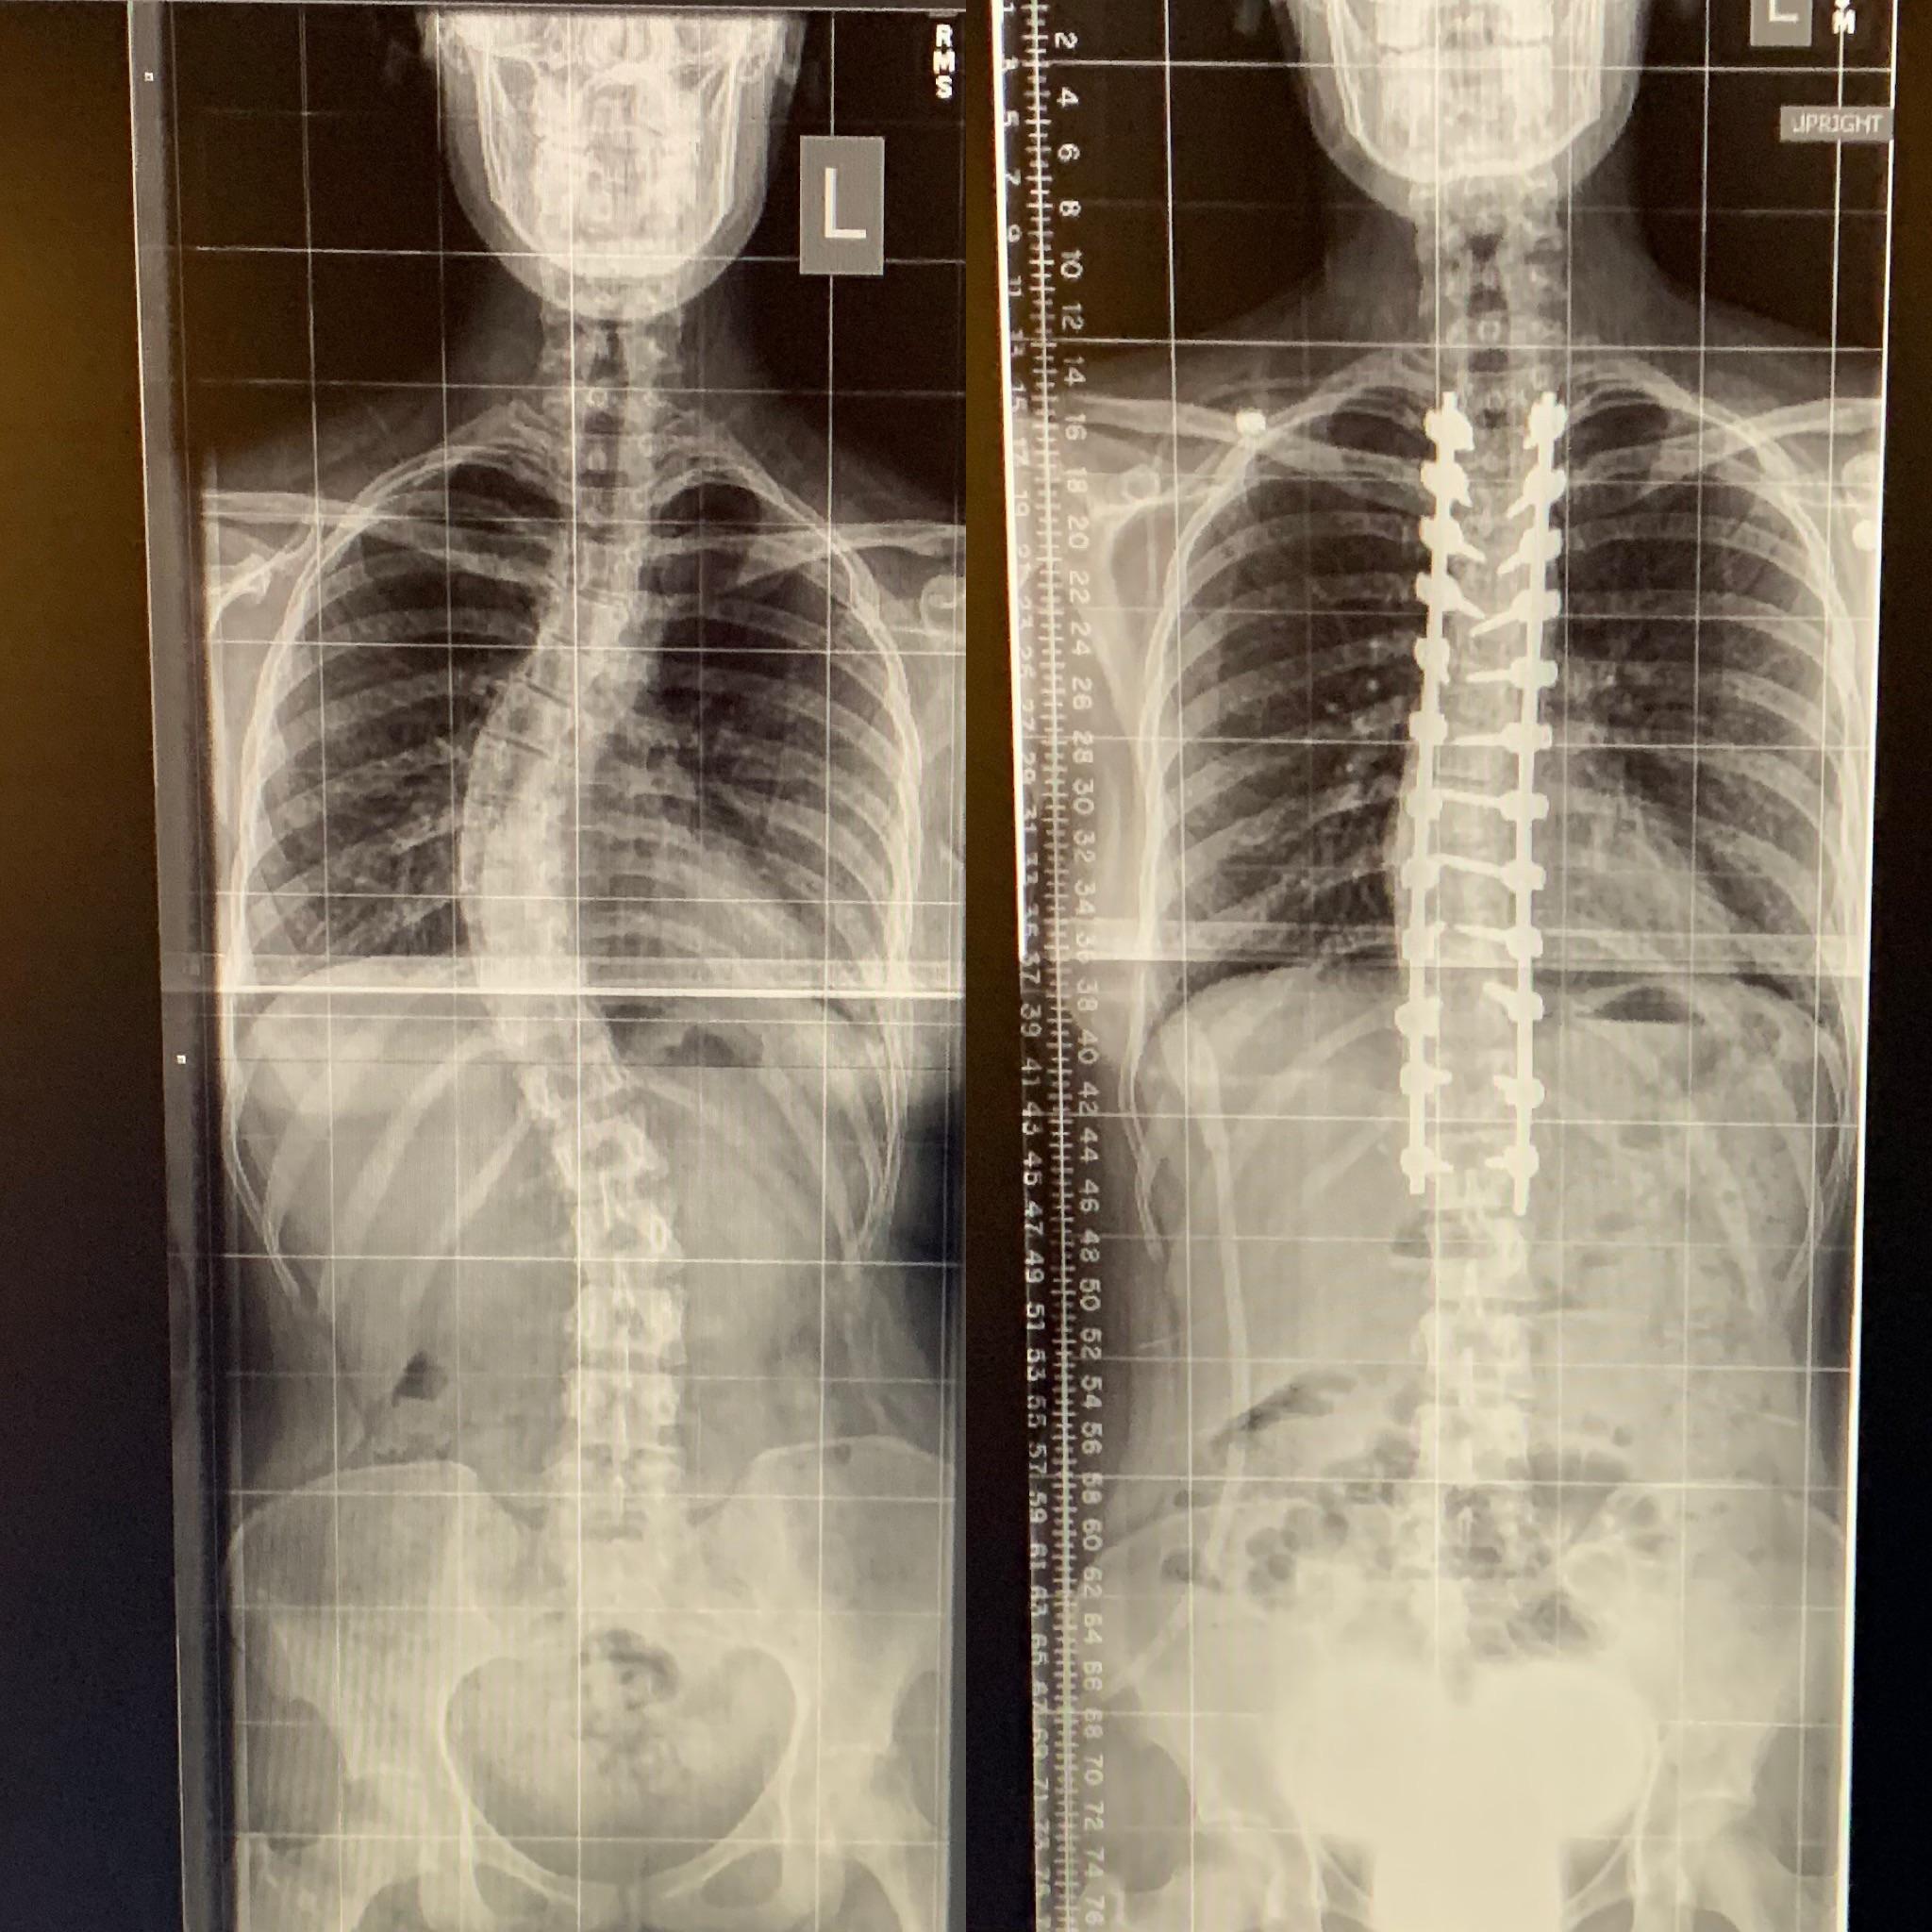

Scoliosis Degrees Of Curvature Chart : Case Study : Bracing and Exercise Rehabilitation ... - Scoliosis is an unnatural, sideways curvature of the spine.. So 10 degrees of curvature with rotation. Scoliosis can be normal up to some degrees. Typically some signs and symptoms of scoliosis can be really variant depending on the, how old is the patient when they're diagnosed and how big the curve actually is. Scoliosis describes any abnormal sideways curvature of the spine. Scoliosis degrees of curvature chart www bedowntowndaytona com.

Scoliosis degrees of curvature chart www bedowntowndaytona com. The asymmetry of the position of the shoulders and shoulder blades is shown. A chart explaining braced vs unbraced progression score. When the degree of sideways curvature exceeds 10 degrees (as measured by the cobb angle), it is diagnosed as scoliosis. Scoliosis degrees of curvature chart google search.

The severity of scoliosis is measured by the degree of. Spinal curvature present after skeletal maturity as a result of any cause. Degree of curve or degree of curvature is a measure of curvature of a circular arc used in civil engineering for its easy use in layout surveying. A chart explaining braced vs unbraced progression score. Scoliosis is an abnormal sideways curvature of the spine with at least a 10 degree cobb angle. Scoliosis describes any abnormal sideways curvature of the spine. A chart explaining braced vs unbraced progression score. A detailed classification of scoliosis — a form and degree of curvature. Scoliosis degrees of curvature chart lovely 12 41 best of. Adolescent idiopathic scoliosis diagnosis and management. 7 types of scoliosis their differences comprehensive guide. A larger, more deforming lower thoracic curve; Adolescent idiopathic scoliosis diagnosis and management.